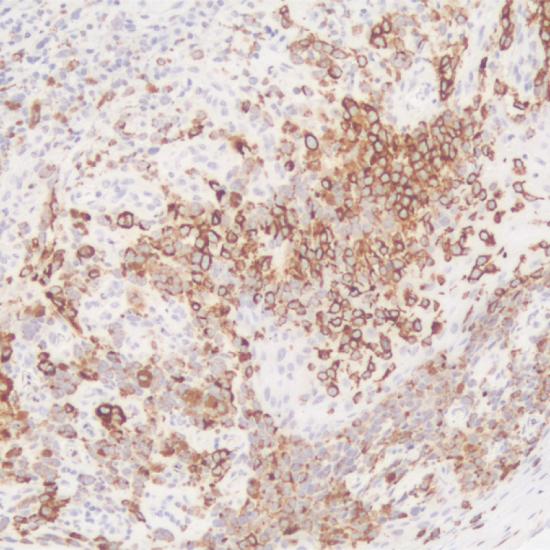

Tyrosinase

Tyrosinase抗體試劑(免疫組織化學(xué)) 閩廈械備20180270號

細(xì)胞漿

黑色素瘤

石蠟

Tyrosinase是一種黑色素細(xì)胞的特異性標(biāo)志物,存在于黑色素細(xì)胞內(nèi)的黑色素小體中,是黑色素小體中的1型膜蛋白,能將酪氨酸轉(zhuǎn)化為黑色素,在黑色素細(xì)胞內(nèi)黑色素形成過程中起重要作用。此抗體主要用于惡性黑色素瘤的研究。